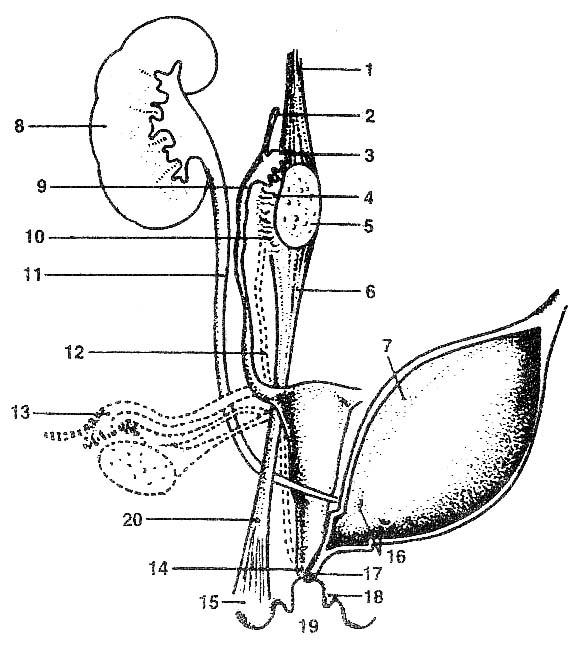

Лабиопластика

Лабиопластика, также известная как лабиопластика, заключается в хирургической модификации больших или малых половых губ, но чаще всего это уменьшение размера малых половых губ (рис.) и является одной из наиболее часто выполняемых процедур FCGS. Часто цель состоит в том, чтобы сохранить контур губ и сохранить цвет губных краев. Различные хирургические методы включают криволинейную резекцию, резекцию V-образным клином, резекцию нижнего клина и реконструкцию верхнего лоскута на ножке, Z-пластику и другие менее используемые методы.

Лабиопластика

Лабиопластика, также известная как лабиопластика, заключается в хирургической модификации больших или малых половых губ, но чаще всего это уменьшение размера малых половых губ (рис.) и является одной из наиболее часто выполняемых процедур FCGS. Часто цель состоит в том, чтобы сохранить контур губ и сохранить цвет губных краев. Различные хирургические методы включают криволинейную резекцию, резекцию V-образным клином, резекцию нижнего клина и реконструкцию верхнего лоскута на ножке, Z-пластику и другие менее используемые методы.